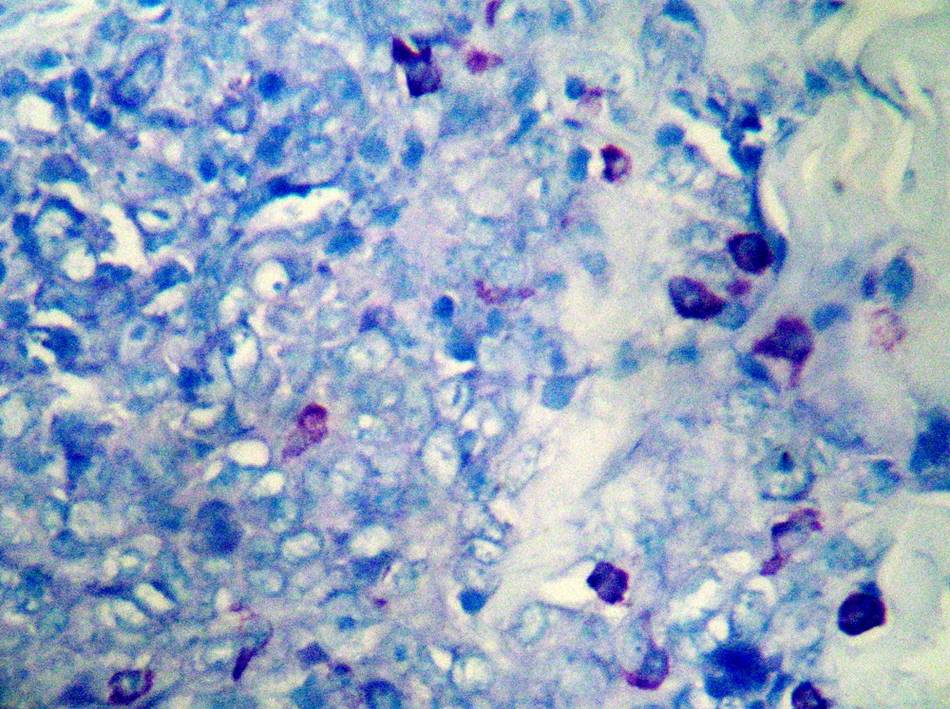

【產品介紹】肥大細胞(Mast?Cell)來源于未分化的間充質細胞,近年來有人認為可能來自胸腺和骨髓。正常多見于小血管周圍,一般在結締組織中都含有少量的肥大細胞,也常見于支氣管周圍和胰的小葉間導管周圍,而在腸系膜的小血管周圍都有大量的肥大細胞。肥大細胞較一般細胞大,直徑約20~30μm。呈圓形或橢圓形;胞核較小,圓形;胞質內充滿粗大并具有異染性的圓形嗜堿性顆粒。

【染色結果】肥大細胞顆粒含有肝素和組織胺等,這些屬于硫酸酯,呈異色性。因此,用易染性染料甲苯胺藍可以使其呈異色性的紅紫色。